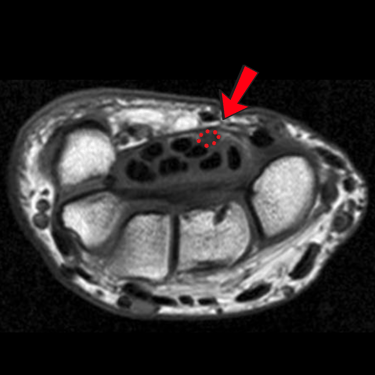

Tratamos compresiones, tumores y lesiones traumáticas de nervios periféricos, como túnel carpiano, neuropatía cubital o tarso, ofreciendo diagnóstico especializado y tratamiento quirúrgico o conservador según cada caso.